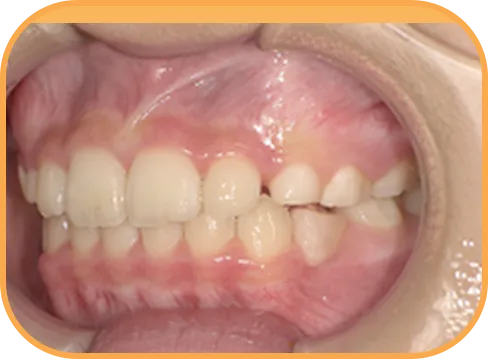

• 正 面

治療後正面からの歯の様子

主 訴

前歯ガタガタ、前歯が大きい

治療内容

インビザライン・ファースト

治療期間

7か月

治療費(税別)

450,000円+診断料5,000円

リスク・副作用

• 親知らずの影響や加齢などによって、凸凹が生じる可能性があります。

• 治療の初期段階では痛みや不快感が生じやすくなりますが、1週間前後で慣れます。

• 顎の成長発育によって、噛み合わせや歯並びが変化する可能性があります。

• 状況により当初予定した治療計画を変更する可能性があります。